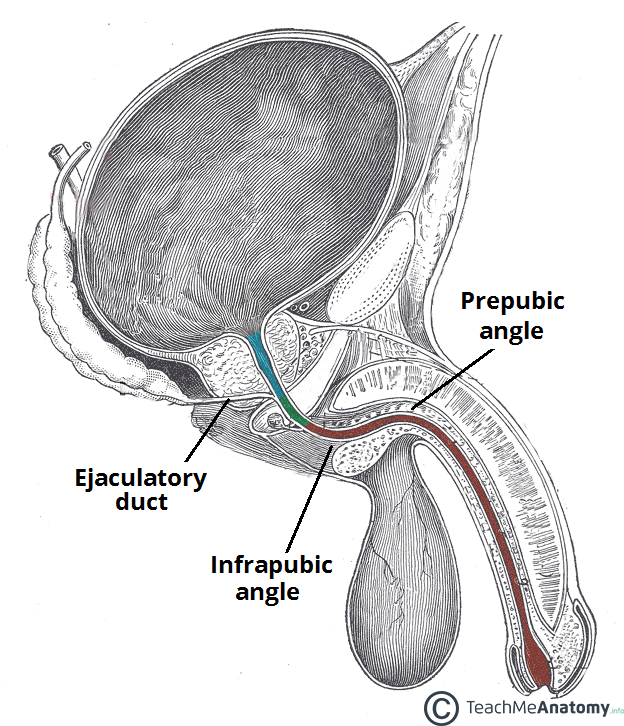

Male Urethra and associated structures

Generally, all humans have urethras. In men, the structure is part of the reproductive system. Located in the penis, it transports urine and semen from the body. This tube in males typically measures about eight inches (about 20.3 cm) long.

Urethral strictures can also cause problems. This condition causes the tube to be abnormally narrow. A continual occurrence of urethritis, scar tissue and inflammation may lead to urethral strictures. Men are typically more prone to have this condition than women. Some common symptoms of this disorder include penis swelling, bloody semen, difficulty urinating, abdominal pain, and dark urine.

A patient examined for this condition may reveal tenderness of lymph nodes in the groin and an enlargement of the prostate in men. Distention of the bladder may also be noted, if the condition affects the ability for urine to pass efficiently. Urine volume measurements may be taken in addition to a urinalysis. As with urethritis, a sexually transmitted disease may lead to urethral strictures, so the patient may additionally be tested for sexually transmitted diseases during the examination.